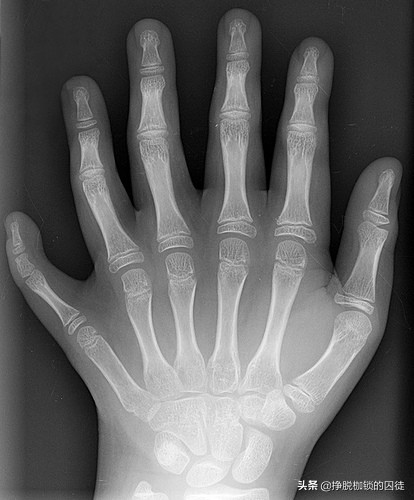

如题图所示,解剖学上,这个具有三节指骨的第六指具有正常的腕部关节结构,独立的骨骼(黄色),肌腱(蓝色),和相对独立的肌肉(绿色和红色)。